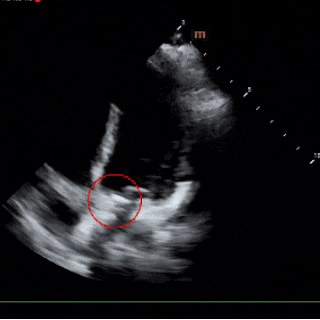

术中复测

左室长轴切面及四腔心切面复测缺损直径均约6mm

锁定后评估

彩色多普勒血流成像显示无残余分流存在

超声下可见封堵器形态良好,多普勒显示无残余分流,封堵成功。